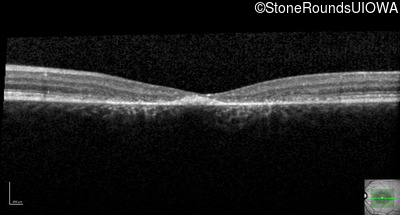

| AR Stargardt Disease | ABCA4 | Asp507Tyr GAT>TAT | IVS40+5 G>A | AR |